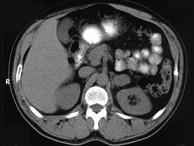

问题 女,34岁,无意中发现血压升高4个月就诊,行CT检查,如图所示,下列说法正确的是()

选项 A.CT示左侧肾上腺区可见一等密度块影,边界清楚 B.增强扫描,该病灶周边明显强化,中心处强化不明显 C.考虑为左肾上腺腺瘤 D.考虑为左肾上腺嗜铬细胞瘤 E.考虑为左肾上腺转移瘤

答案 ABD